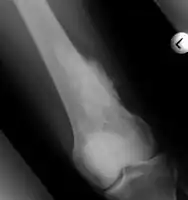

Medical imaging usually shows a well-defined wide-based bony growth on the surface of bone.[5] It can be pedunculated and irregular, giving it a "bizarre" appearance, and is not connected to underlying bone.[2]

X-ray left foot: Bizarre parosteal osteochondromatous proliferation in 2nd toe -